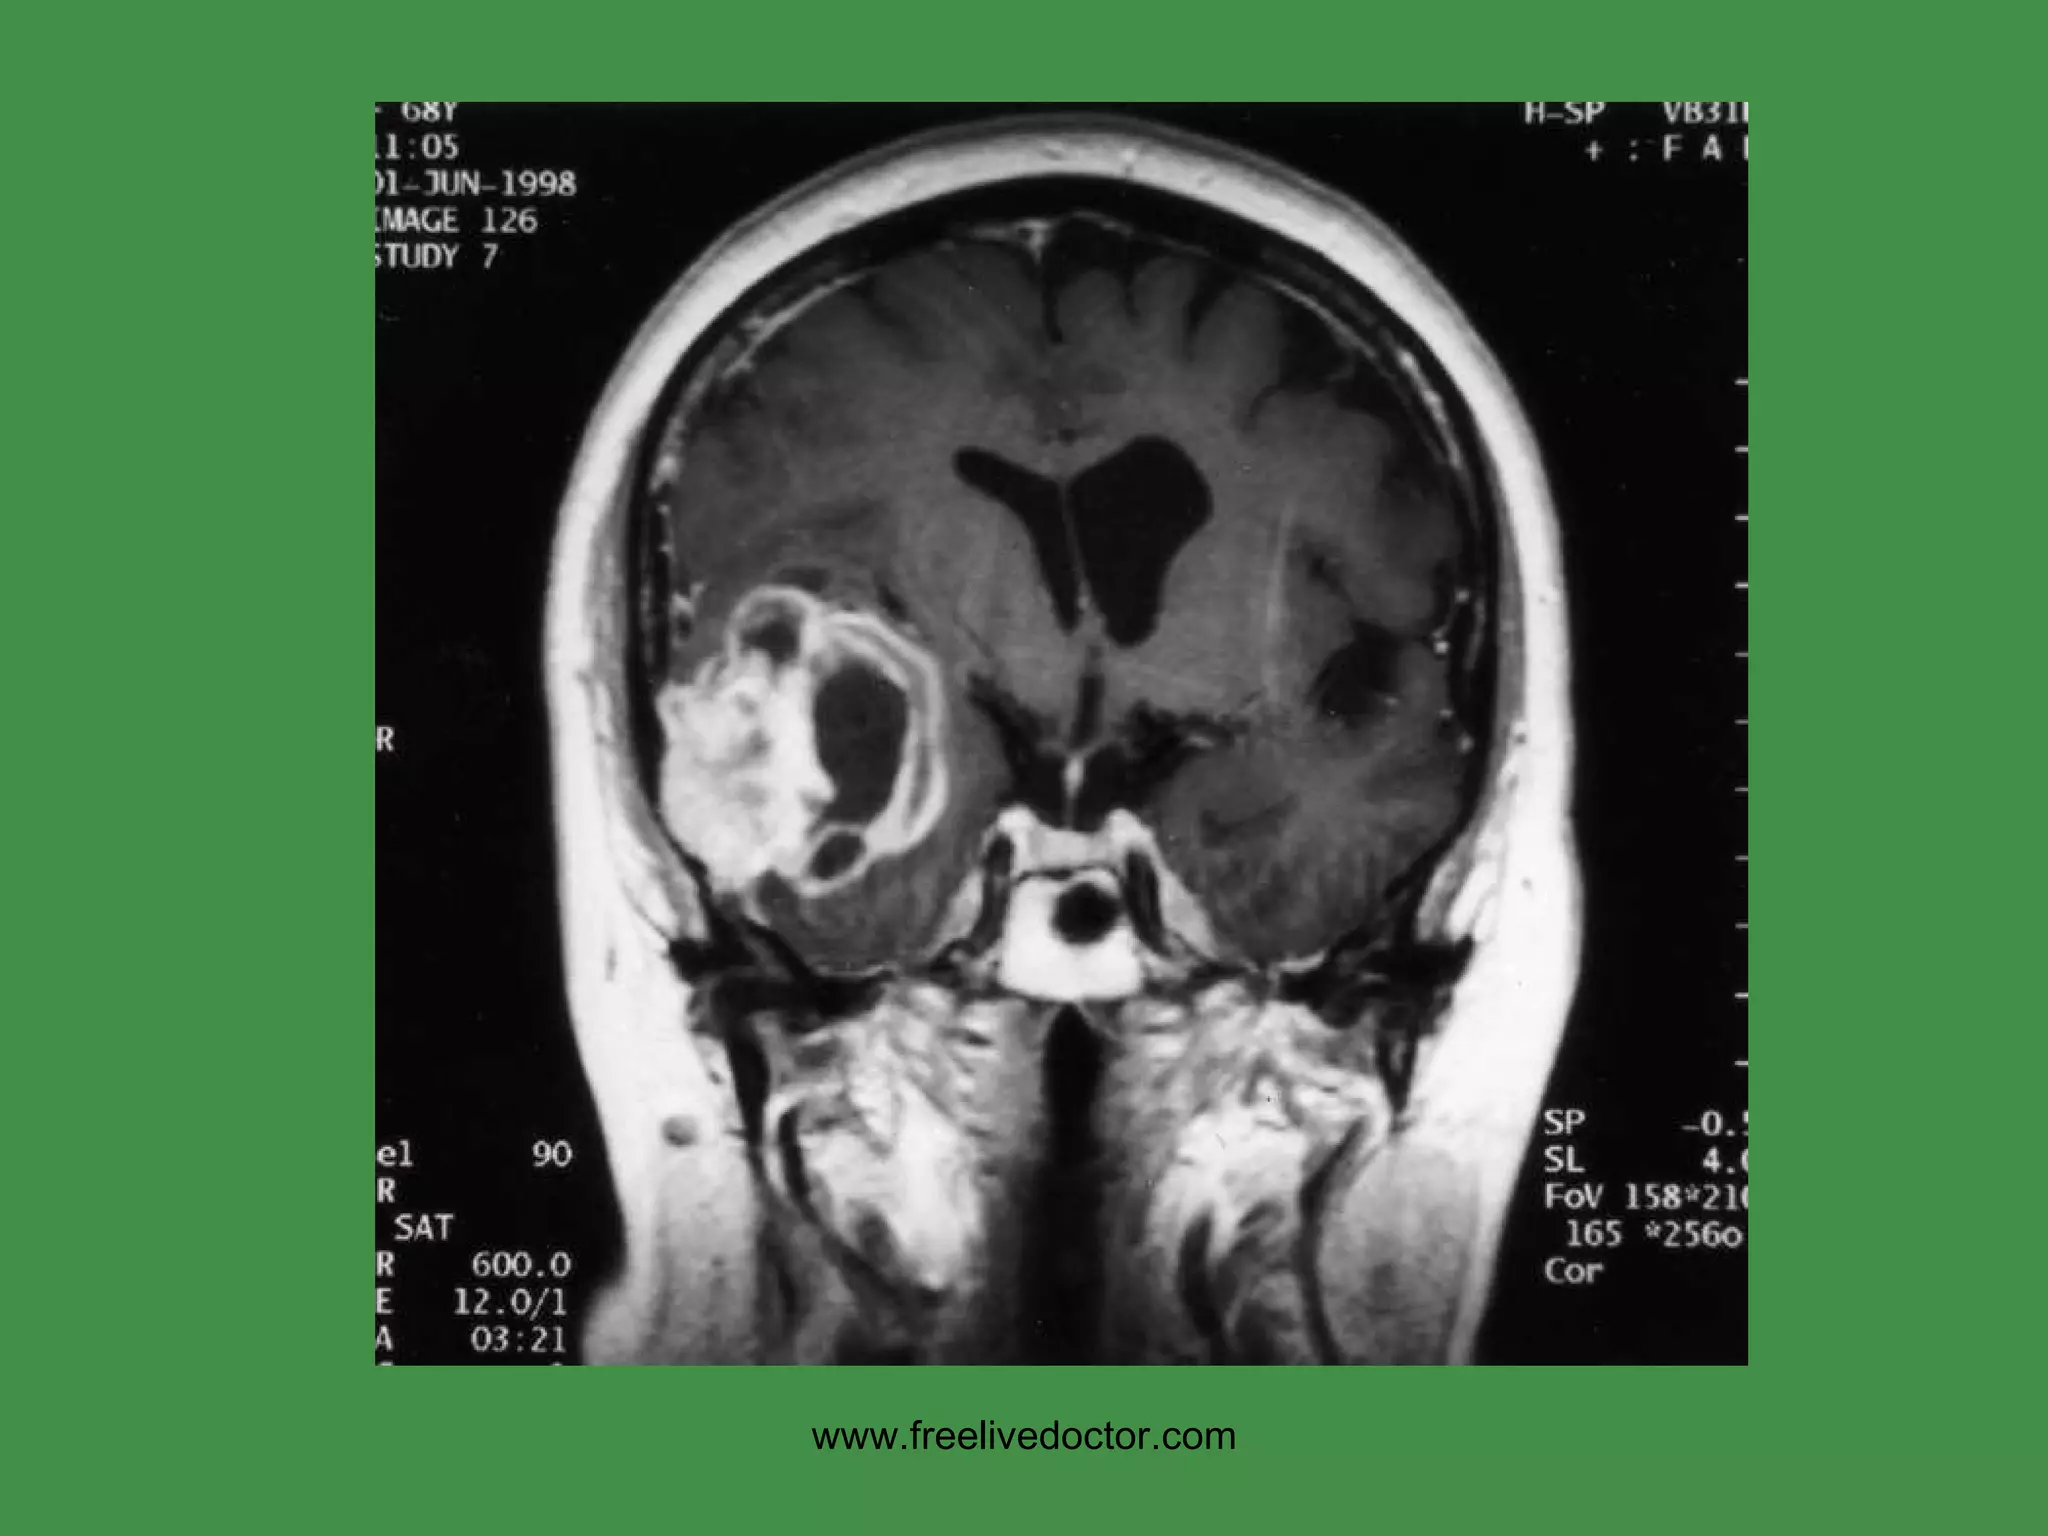

CNS TUMORS Benign? Malignant?, Primary vs. met? Location? Age? X-ray Density?  MIR signals? Calcifications? Vascularity? Necrosis?  Liquefaction? Edema? Compression of neighbors? www.freelivedoctor.com

MENINGIOMAS Occur where dura is Very vascular BENIGN, but…. Can invade skull, etc. Only invade (displace) brain in areas adjacent to dura, i.e., parasagittal, falx, tentorium, venous sinuses Small, firm, and well defined like a SUPERBALL Often (usually?) have  PSAMMOMA   bodies www.freelivedoctor.com

• #162 Arts of this meningioma are denser than bone.

• #163 Note cortical compression from this meningioma.

• #164 Psammoma bodies are diagnostic of meningiomas in brain tumors! What other kinds of tumors have psammoma bodies? Ans: papillary carcinomas, classically in thyroid